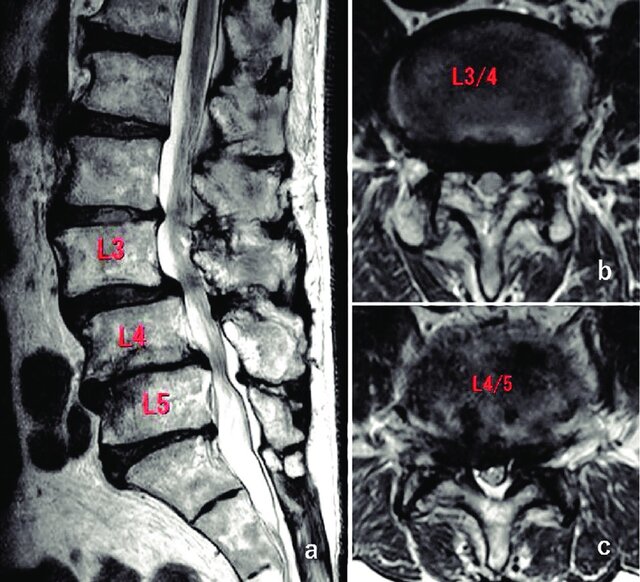

MRI بهترین روش برای تشخیص تنگی کانال نخاعی است. در این روش تصویربرداری پزشکی تمامی جزئیات از جمله ریشههای عصبی و تغییرات نخاع یا تومورهای موجود در ناحیه نخاعی قابل تشخیص است.